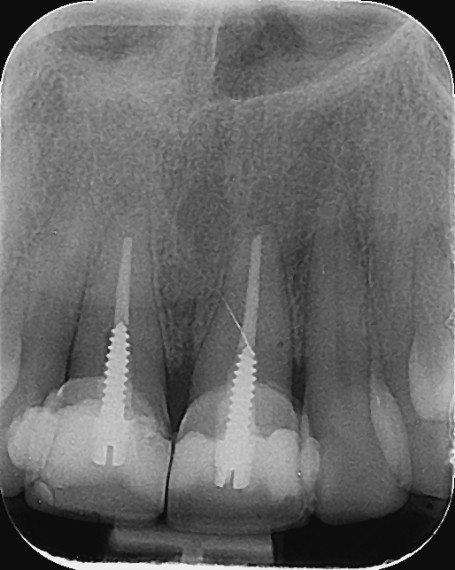

9. What condition can be selected or the root canal treatment of tooth # 1.1?.